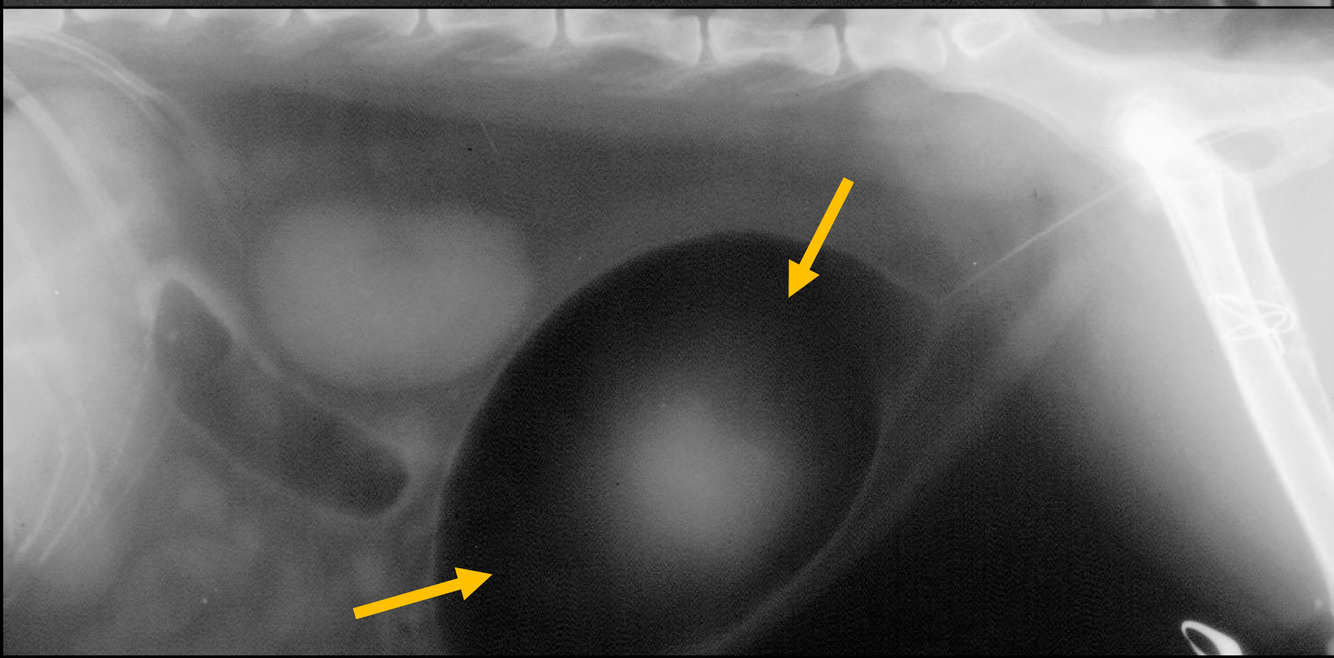

What is being pointed to in this cystourethrograph?

filling defects where contrast is not taken up